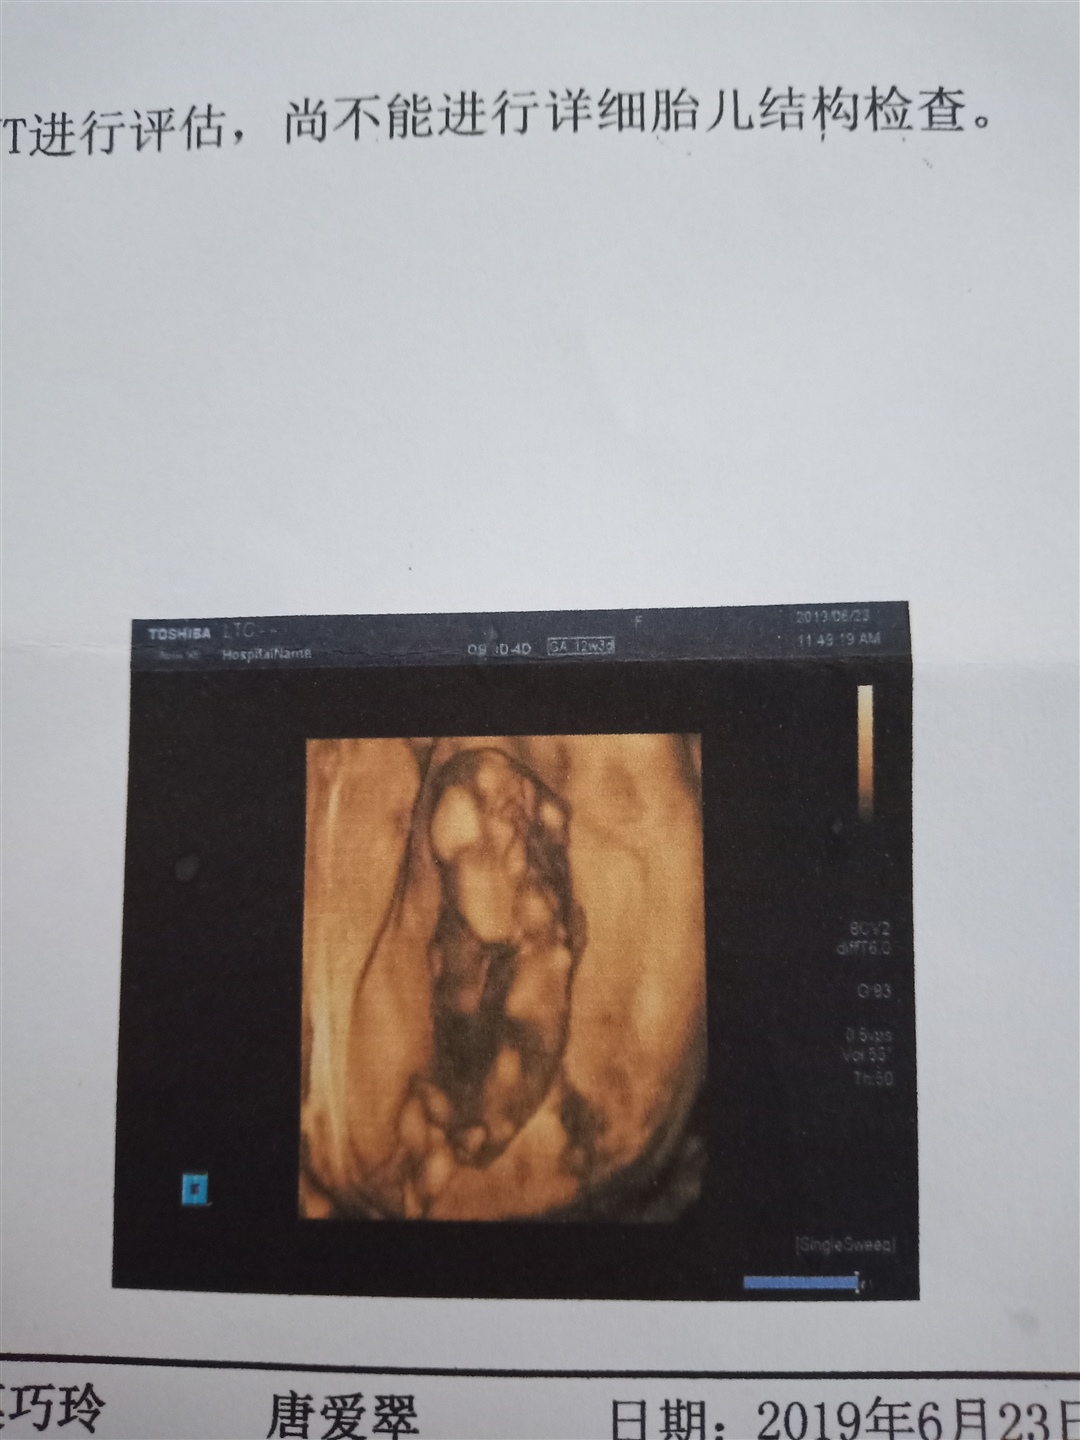

孕12周+1天